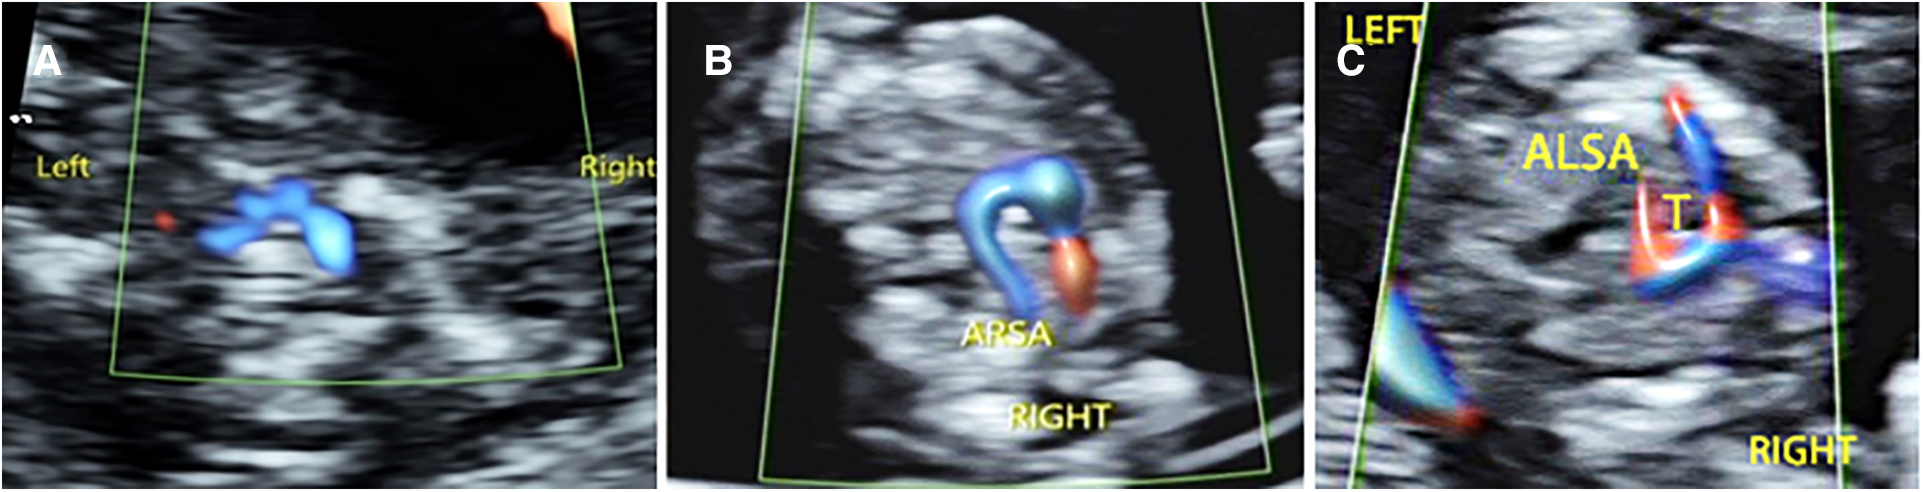

Among the 176 fetuses with CHD, 10 fetuses had an abnormal upper abdominal transverse section. According to the integrity of the fetal abdominal wall and the spatial position of four U-shaped structures (gastric bleb, inferior vena cava, aorta, and spine), four abnormal image patterns of UAb transverse section were found, which could be seen in normal cases, situs inversus, left isomerism syndrome, and right isomerism syndrome (Figure 4). According to the location, size, cardiac axis, the central crisscross structure of the heart and the size and direction of blood flow bundles, 16 kinds of 4CV section abnormal patterns were found (Figure 5). According to the number of large arteries, the relationship between the pulmonary artery and the aorta, the diameter of the pulmonary artery and the aorta, and the direction of blood flow between the ductus arteriosus and the aortic arch, eight abnormal patterns of 3VT section were found (Figure 6). According to the course of bilateral subclavian arteries, two abnormal patterns of BSa sections were found (Figure 7).

Abnormal ultrasound image pattern of the bilateral subclavian artery section. (A) Normal bilateral subclavian arteries are in front of the trachea, and they form a “bow” structure. (B) BSa-1 pattern: The right subclavian artery originates from the descending aorta, bypasses the trachea, and then runs to the right. (C) BSa-2 pattern shows that the left subclavian artery originates from the descending aorta and is circumvented behind the trachea to the left.